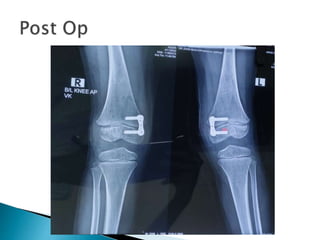

 In our patient growth potential remaining

So,Guided growth modulation

Figure of 8 plate 16mm applied B/L

Now this is standard treatment for skeletally

immature

Removal?